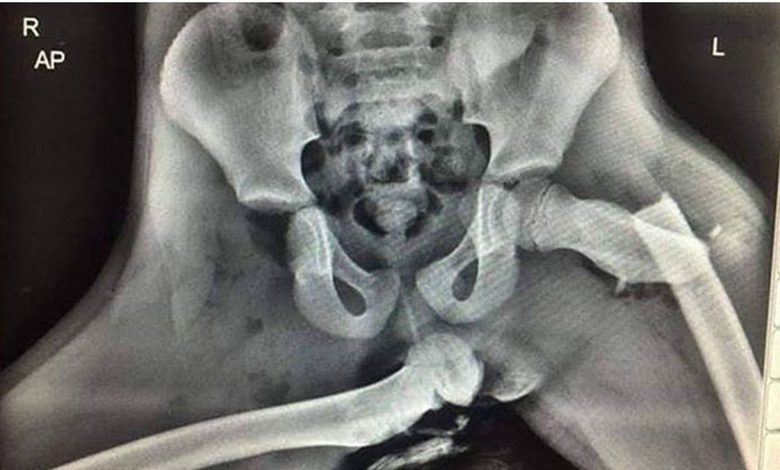

Όπως μπορείτε να δείτε από τη φωτογραφία που ακολουθεί σε μια πρόσκρουση ο αερόσακος του συνοδηγού ανοίγει και πιέζει με πολύ μεγάλη δύναμη τα πόδια. Οι επιπτώσεις μιας τέτοιας βίαιης μετακίνηση των ποδιών φαίνονται στην ακτινογραφία που έχει κυκλοφορήσει στο παρελθόν στο Twitter.

Όπως είπε χειρούργος ορθοπεδικός που είδε την ακτινογραφία στην αριστερή πλευρά υπάρχει κάταγμα του αυχένα του μηριαίου και στη δεξιά εξάρθρωση του μηρού. Παράλληλα η συγκεκριμένη στάση μπορεί να οδηγήσει και σε σοβαρό τραυματισμό του κεφαλιού, μιας και κινείται προς τα εμπρός και μπορεί να συγκρουστεί με τα πόδια που μετατοπίζονται βίαια προς τα πίσω.

Here is an X-ray of horrific injuries sustained to the front seat passenger who had their feet on the dashboard at the time of a collision. If you see your passenger doing it stop driving and show them this. pic.twitter.com/f3XCT8ePvi